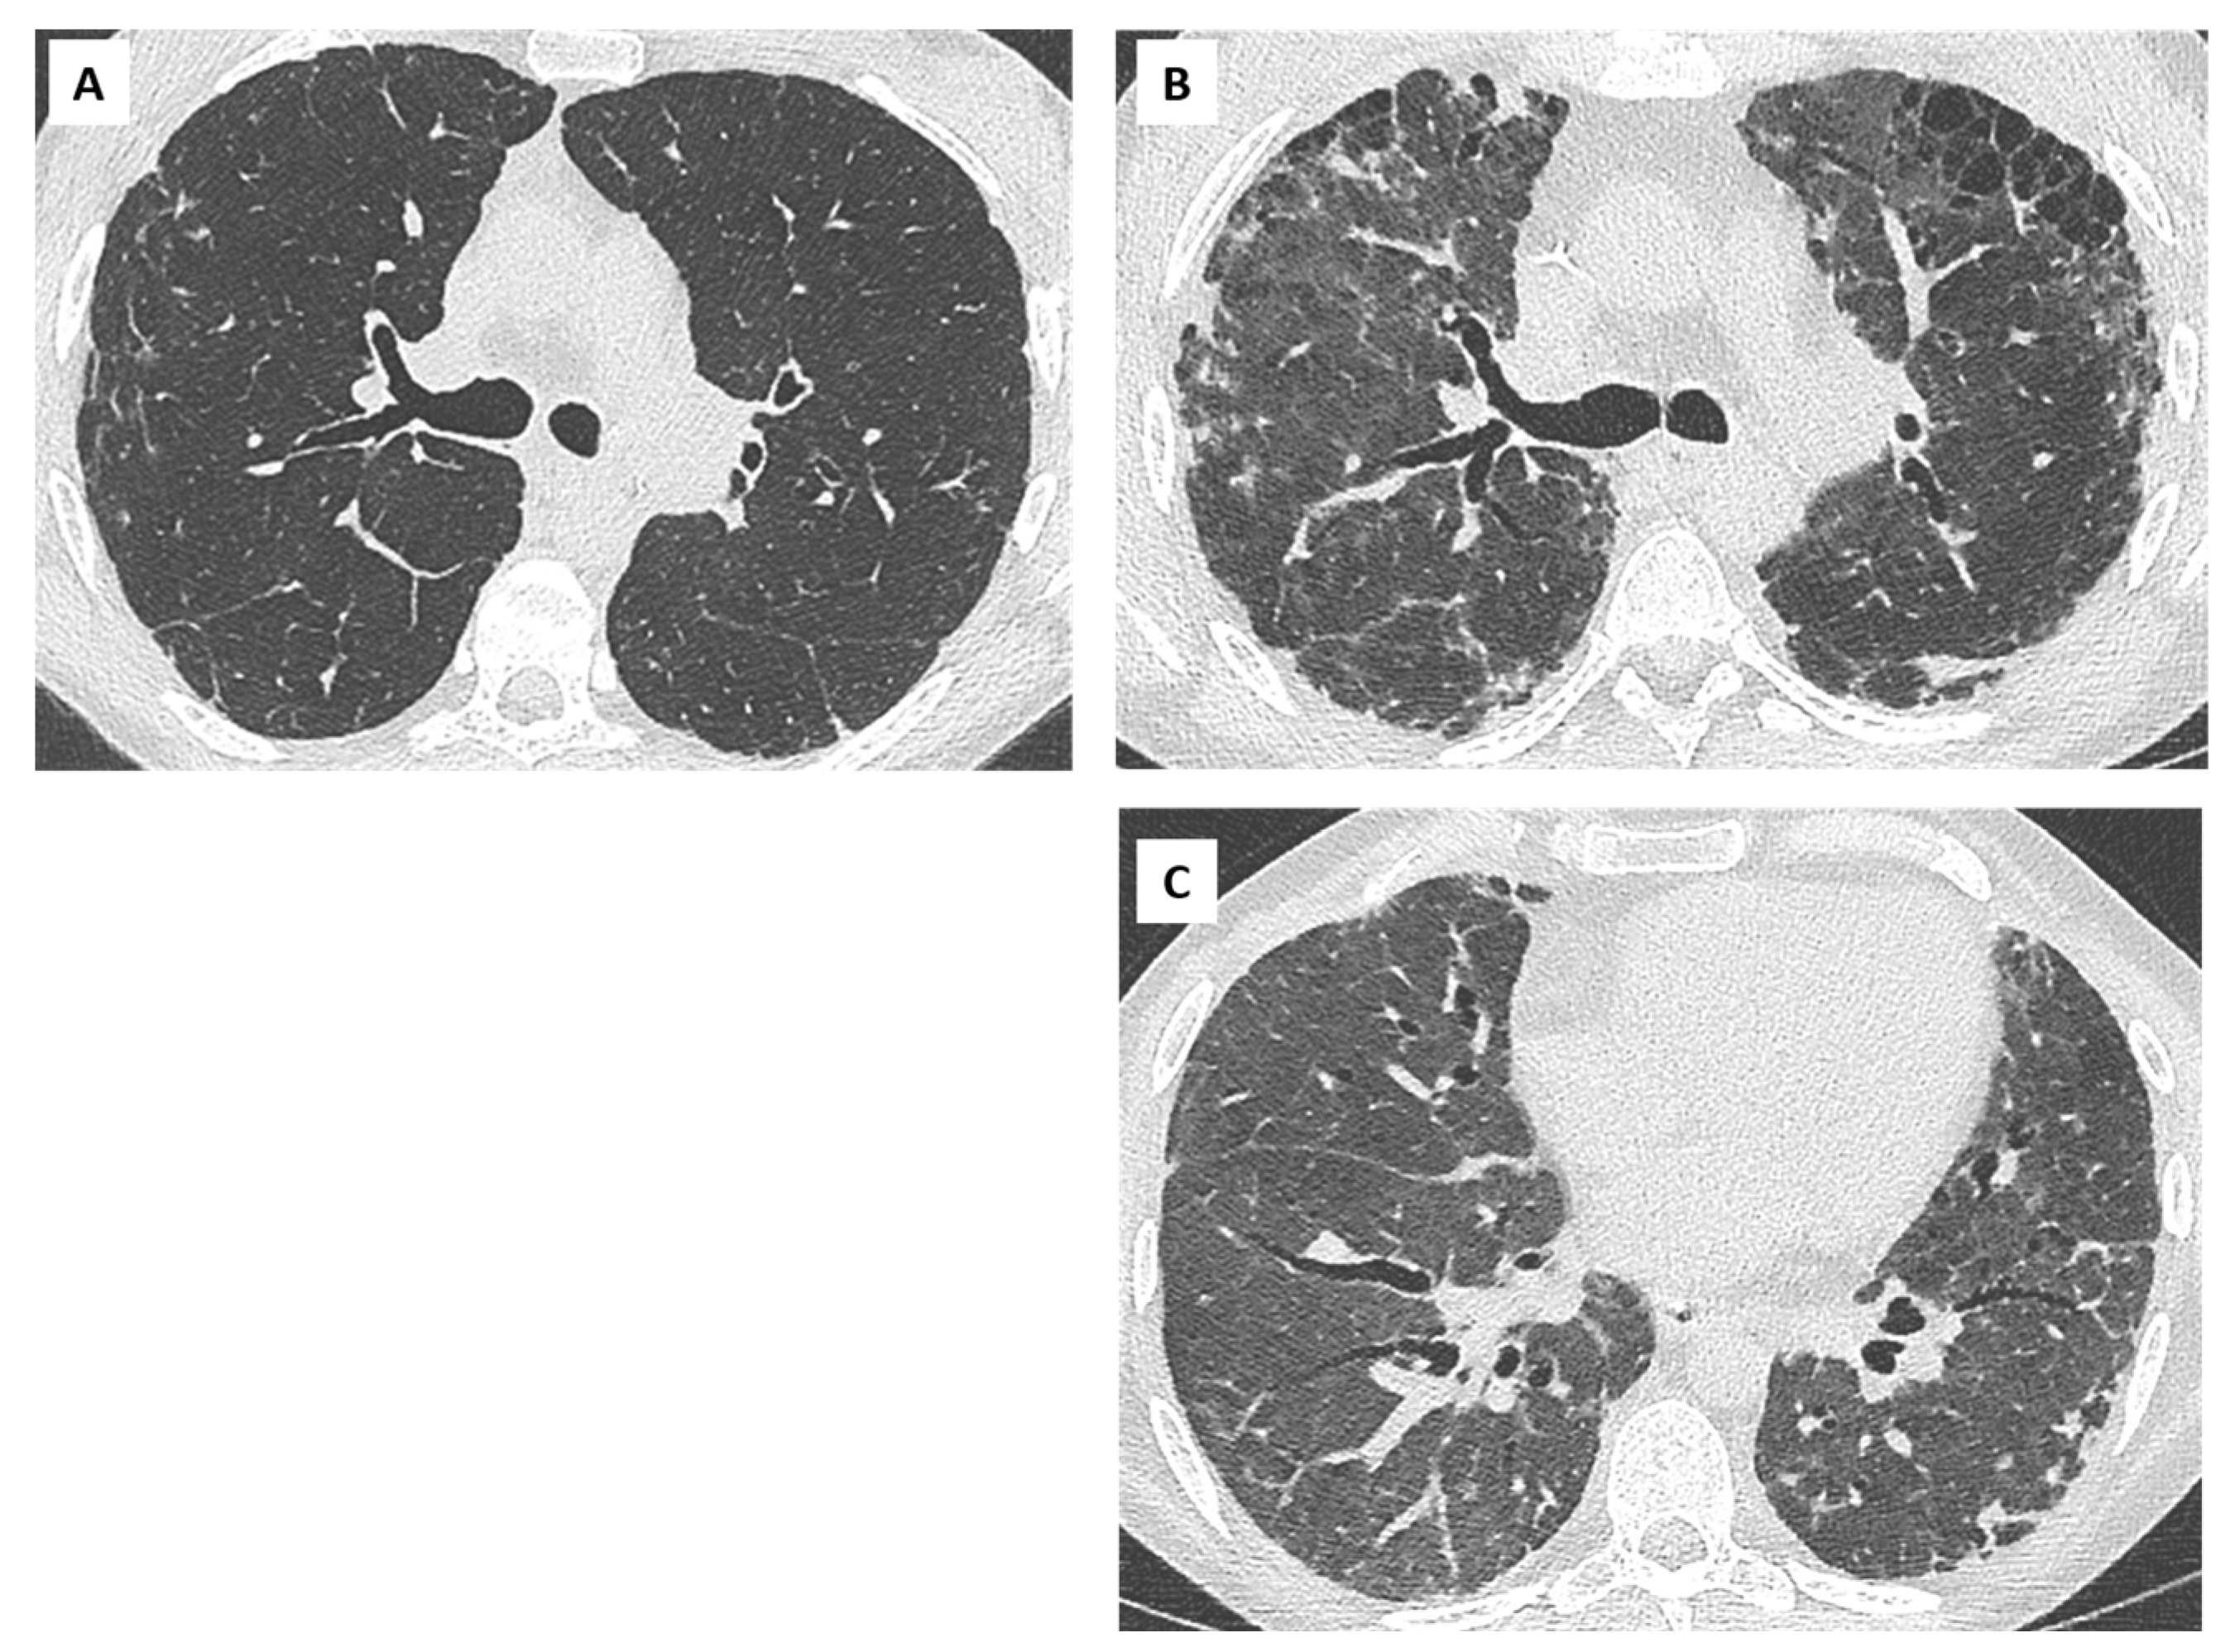

- Dubbeldam, A.; Barthels, C.; Coolen, J.; Verschakelen, J.A.; Verleden, S.E.; Vos, R.; Verleden, G.M.; De Wever, W. Restrictive allograft syndrome after lung transplantation: New radiological insights. Eur. Radiol. 2016, 27, 2810–2817. [Google Scholar] [CrossRef]

- Sato, M.; Hwang, D.M.; Waddell, T.K.; Singer, L.G.; Keshavjee, S. Progression pattern of restrictive allograft syndrome after lung transplantation. J. Heart Lung Transplant. 2013, 32, 23–30. [Google Scholar] [CrossRef]

- Ofek, E.; Sato, M.; Saito, T.; Wagnetz, U.; Roberts, H.C.; Chaparro, C.; Waddell, T.K.; Singer, L.G.; Hutcheon, M.A.; Keshavjee, S.; et al. Restrictive allograft syndrome post lung transplantation is characterized by pleuroparenchymal fibroelastosis. Mod. Pathol. 2013, 26, 350–356. [Google Scholar] [CrossRef]

- von der Thüsen, J.H.; Vandermeulen, E.; Vos, R.; Weynand, B.; Verbeken, E.K.; Verleden, S.E. The histomorphological spectrum of restrictive chronic lung allograft dysfunction and implications for prognosis. Mod. Pathol. 2018, 31, 780–790. [Google Scholar] [CrossRef] [PubMed]

- Montero, M.A.; Osadolor, T.; Khiroya, R.; Salcedo, M.T.; Robertus, J.L.; Rice, A.; Nicholson, A.G.; Roman, A.; Monforte, V. Restrictive allograft syndrome and idiopathic pleuroparenchymal fibroelastosis: Do they really have the same histology? Histopathology 2017, 70, 1107–1113. [Google Scholar] [CrossRef] [PubMed]

- Verleden, S.E.; Vasilescu, D.M.; McDonough, J.E.; Ruttens, D.; Vos, R.; Vandermeulen, E.; Bellon, H.; Geenens, R.; Verbeken, E.K.; Verschakelen, J.; et al. Linking clinical phenotypes of chronic lung allograft dysfunction to changes in lung structure. Eur. Respir. J. 2015, 46, 1430–1439. [Google Scholar] [CrossRef]

- Verleden, S.E.; Von Der Thüsen, J.; Van Herck, A.; Weynand, B.; Verbeken, E.; Verschakelen, J.; Dubbeldam, A.; Vanaudenaerde, B.M.; Vos, R.; Verleden, G.M.; et al. Identification and characterization of chronic lung allograft dysfunction patients with mixed phenotype: A single-center study. Clin. Transplant. 2020, 34, e13781. [Google Scholar] [CrossRef]